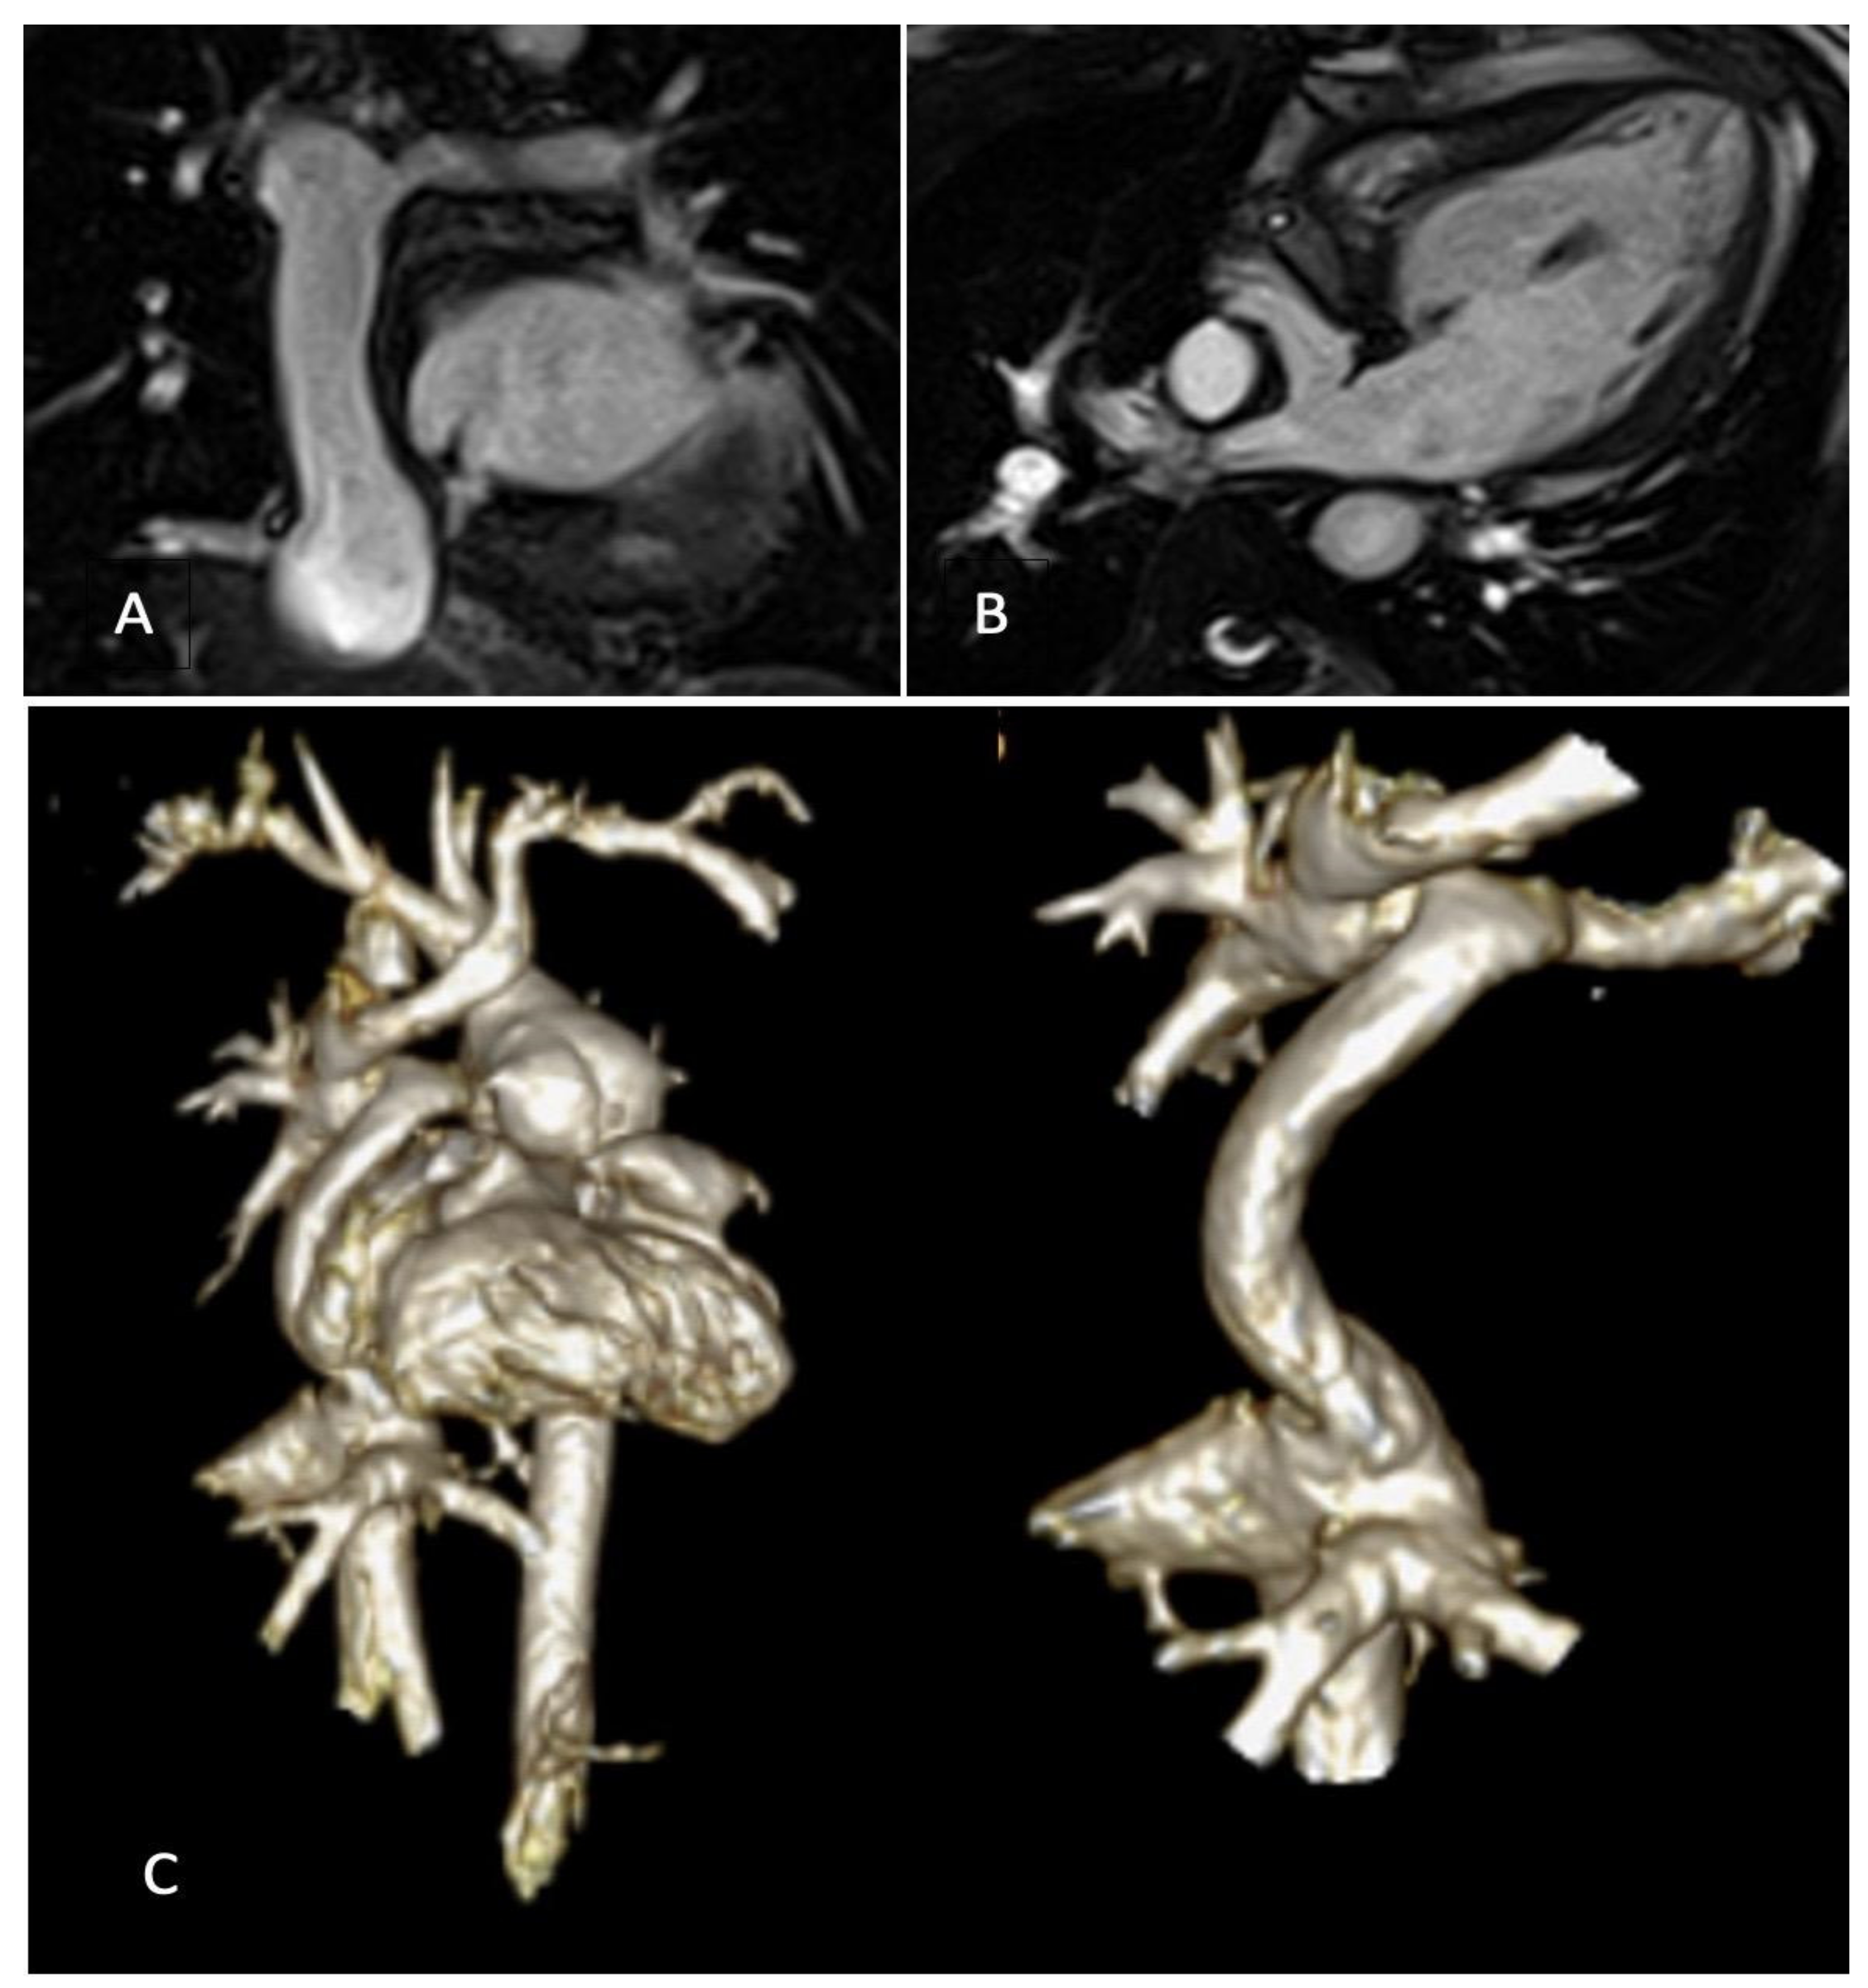

Moreover, 3D whole-heart SSFP allows a comprehensive and detailed evaluation of intracardiac and extra-cardiac morphology; it permits the visualisation of the arterial and venous systems together with their collaterals and the measurements of their vessels’ size. In adolescents and adults, it is acquired during mid-diastole when the heart is still, but, in children, due to the high heart rate, it may be necessary to plan it at the end-systolic phase of the cycle Figure 3.

Figure 3. (A) bSSFP image of Fontan conduit; (B) modified bSSFP four-chamber view with small VSD in the IVS; (C) 3D reconstruction of Fontan circuit.